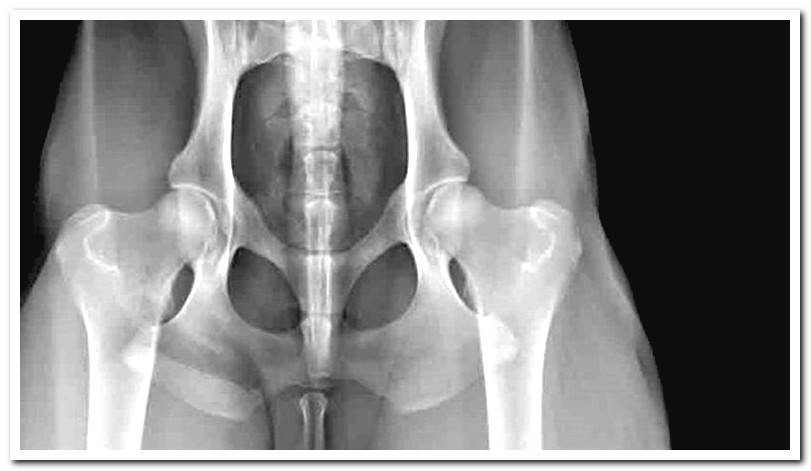

The test of choice is radiography. To get a good shot, it is necessary to sedate the animal. Depending on the severity of the damage, different degrees of dysplasia are distinguished: mild, moderate or severe.

It is possible to see injuries in the area such as arthritis, bone spurs or wear, secondary to pathology. If arthritis is detected, the condition is irreversible.